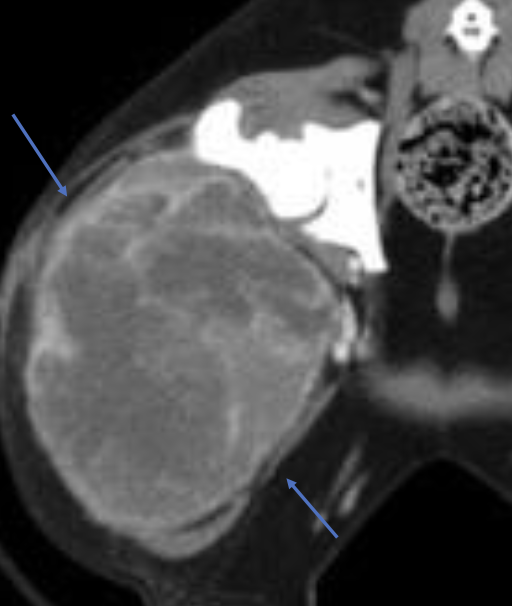

what is the appearance of hemangiosarcoma lesions in the abdomen using abdominal ultrasound?

-heterogenous (hypoechoic to targetoid to mixed)

-cavitation

- +/- peritoneal effusion